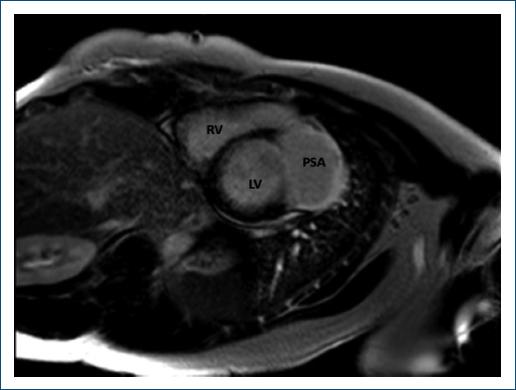

Cardiac magnetic resonance revealed a normal LV size, 35% LVEF, and a LVP of 65 × 40 mm with thrombus formation, highly suggestive of ischemic etiology (Fig. 1). The left anterolateral ventricular wall perforation was contained solely by fibrosis of the pericardium, having a high risk of rupture. Coronary angiography revealed a Type 2 dissection of the left main artery extending into the left anterior descending artery and circumflex artery, which were both occluded (Fig. 2). After the diagnosis, surgical intervention (Fig. 3) was success with pseudoaneurysm exclusion and myocardial revascularization (Fig. 4).

Figure 1 Transversal view of l LV pseudoaneurysm in cardiac magnetic resonance. RV: right ventricle; LV: left ventricle; PSA: pseudoaneurysm.